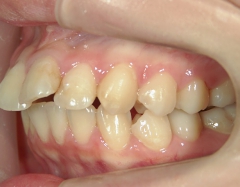

矯正歯科 治療後矯正歯科 プチワイヤー矯正 治療後矯正歯科(プチワイヤー矯正)治療後

矯正歯科 治療後

no.6_8296_治療後_右.jpgno.6_8296_治療後_正面.jpgno.6_8296_治療後_左.jpg